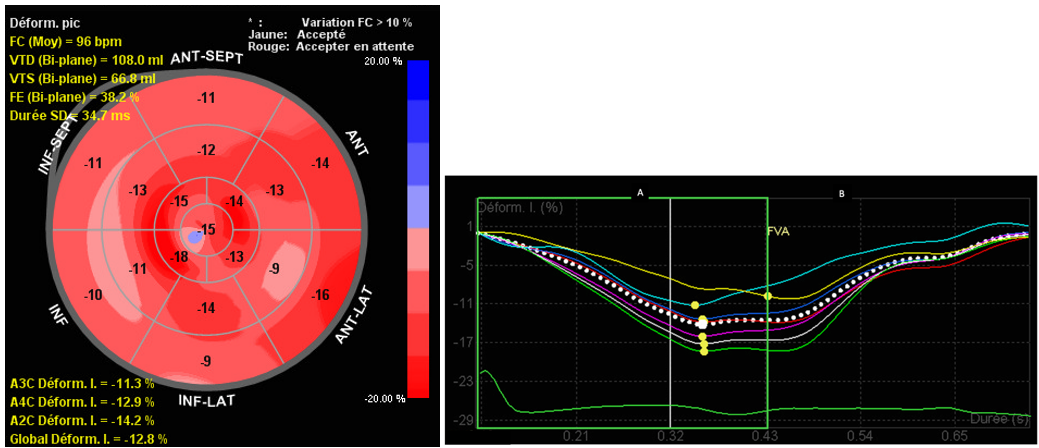

A cardiac ultrasound showed reduced contractility of the left ventricle, with left ventricular ejection fraction (LVEF) of 38% , global longitudinal strain (GLS) of -12% (Figure 2), along with significant spontaneous contrast and dilated left atrium. Additionally, two masses were identified at the apex of the left ventricle (LV) (Figure 3), and a third, larger mass was attached to the lateral wall of the right ventricle (RV) (Figure 4). The appearance of these masses was highly suggestive of thrombus, thus anticoagulation treatment was initiated.

Figure 2: Altered GLS calculated from the apical long axis, four-chamber and two-chamber view.

Another possible mechanism of thrombosis in our patient is myocarditis. Myocardial involvement in adult SLE is rare (9% of patients); it can range from a fatal fulminant form to a long-lasting asymptomatic form [5]. In young patients, this involvement is more common and severe. In cases of severe lupus activity, myocardial damage occurs at an early stage of the disease and is usually associated with lupus nephritis [6]. Some of the main factors implicated are coronary atherosclerosis, hypertensive cardiomyopathy, and side effects of specific treatments[7]. Diagnosis is based on clinical examination, biochemical markers, cardiac imaging, and ultimately endomyocardial biopsy. In our patient, echocardiography confirmed myocardial involvement with altered GLS and reduced LVEF. Additionally, globally non-systematized hypokinesis of the left ventricle was highly suggestive of lupus myocarditis.